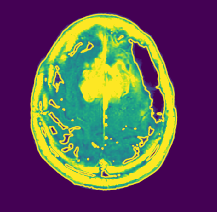

Contour calibration: Regarding MRI images, it is desired to have a higher contrast in the area of interest and lower on the rest. The images that are analyzed till now are in gray scale, hence the different variations in textures are not visible. To know the depth or height of a 3D plane contour lines can be used. It is a function of two variables in a curve along which the function has a constant value so that the curve joins points of equal value. A gray-scale image can also be seen as a 3D representation of the values ranging from 0 to 255 for each pixel of which contour can be plottedkim2014relationship . In this experiment, the MRI has a size of 150 ×\times150 and the contour line can be used to define various colors to the images with varying gray scale. An example showing the contour plot for an MRI sample is shown in Fig. 6(a).

(a) Contour plot for gray scale MRI image.

To compare the preprocessed MRI images, visual inspection of image outline, the colour of the various regions needs to be explored. The green colour represents low intensity, yellow signifies higher intensity and brown lines indicate higher variation in the intensities over that region. Figure-10 shows a transition of the various stages of the proposed preprocessing for a normal brain. The contour of the normal brain produces many yellow lines as seen in Figure-10(b). But when compared with the difference contour, the regions are equally coloured without any yellow lines. Further, no brown edge is seen in the final image as seen in Figure-10(d). This means the proposed preprocessing can normalize the lower ranges of intensity difference (yellow lines).

Figure 11 shows a transition of the various stages of the proposed preprocessing for a benign brain neoplasm. The contour of the benign brain produces many yellow regions as shown in Fig. 11(b). But when compared with the difference contour, the less interesting regions are colored green with a brown border. Further, a brown edge with yellow is is seen in the final image where the benign neoplasm is present as seen in Fig. 11(d). This means the proposed preprocessing can intensify the regions with benign neoplasm than the other regions.

Figure 12: Proposed preprocessing applied over malignant MRI images.

Figure-12 shows a transition of the various stages of the proposed preprocessing for a malignant brain neoplasm. The contour of the malignant brain produces a centralized yellow region as seen in Fig. 12(b). But when compared with the difference contour, the less interesting regions are colored green with a brown border as previously seen with benign MRI. Further, a brown edge with yellow is is seen in the final image where the malignant neoplasm is present as seen in Fig. 12(d). The proposed preprocessing can outline the portion with the brain tumor effectively, even if the tumor is discreetly spaced. Further, many preprocessing techniques tend to over soften the image during the noise removal process to get better accuracy, but this changes the original image features. This proves to be beneficial when detecting the presence of neoplasm but during the classification of the severity, this process fails to get good results. But in the case of the proposed preprocessing, the final output MRI image is free of over softness and hence the features are preserved better.